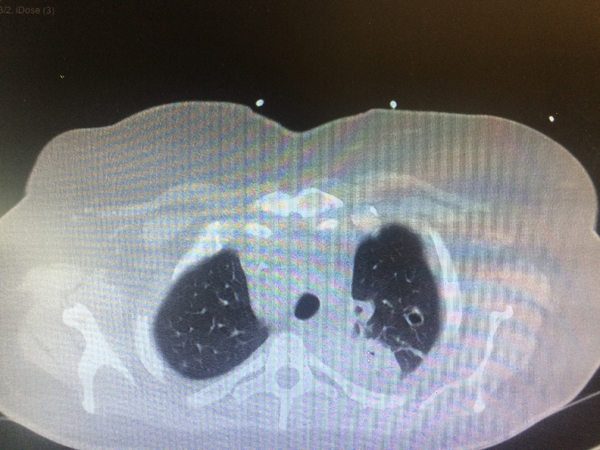

Voici les images du scanner thoracique.

Question 11 : Quelle est votre suspicion diagnostique ?

Syndrome septique chez un porteur de valve prothétique pulmonaire, examen direct suggérant un sepsis à staphylocoques (germe pourvoyeur d’EI), nombreux emboles pulmonaires excavés